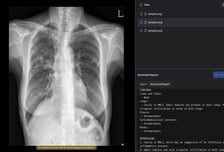

AI로 흉부X선 예비소견서 생성…숨빗AI, 식약처 3등급 인허가 획득

[스타트업에 대한 보다 다양한 기업정보는 유니콘팩토리 빅데이터 플랫폼 '데이터랩'에서 볼 수 있습니다.] 의료 AI(인공지능) 기업 숨빗AI가 식품의약품안전처로부터 흉부X선 예비소견서 생성 솔루션 '에어리드-씨엑스알'(AIRead-CXR)에 대한 3등급 인허가를 획득했다고 2일 밝혔다. AIRead-CXR은 국내외에서 확보한 약 1400만건의 데이터를 학습해 다양한 병원 환경에서 촬영된 PA(뒤에서 앞으로 찍는 방식) 또는 AP(앞에서 뒤로 찍는 방식) 흉부X선에 대해 안정적으로 예비소견서를 제공한다. 검증된 57개 소견 및 질환에 대해 높은 수준의 판독보조 성능을 제공할 뿐 아니라 이외의 다양한 영상 소견도 해석·언급할 수 있다. 임상 현장의 실제 워크플로우를 반영해 의료진이 보다 효율적으로 판독 업무를 수행할 수 있도록 설계됐다.